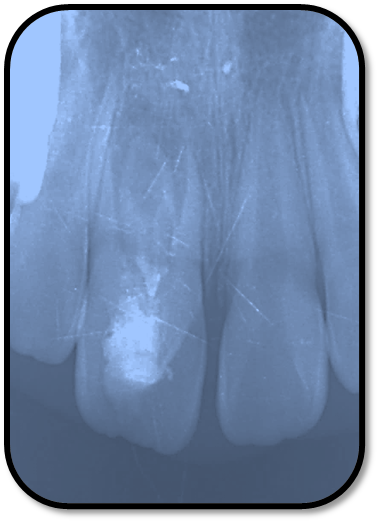

检查: 右上1牙冠略宽大,舌侧见粗大的畸形舌尖,叩痛(++),松Ⅰ°,唇侧牙龈红肿前庭沟膨隆扪痛,挤压唇侧龈缘溢脓,冷热测无反应,右侧上下1侧方颌,正中颌颌创伤。 X线:右上1发育7-8期,根管平行状,根尖孔宽大,约5-6mm宽,根尖周低密度影。髓腔根管宽大内见倒置牙影像,倒置牙可见髓腔。 余牙未见异常 6均已萌出建颌

初步诊断:右上1牙内陷根尖炎,颌创伤 治疗计划:1、口腔卫生宣教 2、右上1调合,牙髓再血管化治疗, 成年后烤瓷贴面修复 3、定期复查(1月、3月、6月--) 处置:右上1STA必兰局麻下舌侧开髓,查得两根管,一个是长扁根管,一个是牙中牙内陷盲袋形成的椭圆根管,拔根髓不成形,5.25%次氯酸钠冲洗浸泡根管5-10分钟,超声根管荡洗,反复3次,2%CR冲洗根管,隔湿干燥后,封Ca(OH)2。调合,去除咬颌创伤。 复诊:隔2周复诊,行5.25%次氯酸钠冲洗浸泡根管5-10分钟,超声根管荡洗,反复3次,2%CR冲洗根管,隔湿干燥后,封Ca(OH)2。 此后复诊每隔1周行2.5%次氯酸钠冲洗浸泡根管5-10分钟,超声根管荡洗,反复3次,2%CR+NS冲洗根管,隔湿干燥后,封Ca(OH)2。 2个月后:患牙症状消失,临床检查无阳性体征,去暂封无渗出,2.5%次氯酸钠冲洗浸泡根管5-10分钟, 2%CR+NS冲洗根管,隔湿干燥后,用无菌30#根管锉超出根尖3-4mm刺破根尖组织出血,待形成血凝块后,置MTA,GIC,冠方树脂严密充填。

随访复查: 治疗完成后1个月复查:右上1临床检查无阳性体征,叩痛(—),冷测无反应,无松动,牙龈无红肿,充填物完好,牙冠略有变色, X线检查:牙根根继续发育,可见钙化影像形成,如图示 治疗完成后7个月复查:临床检查无阳性体征,充填物完好,牙冠变色局部发黑,叩痛(—),冷测无反应,无松动,牙龈无红肿,临床及 X线检查:牙根继续发育,如图示 治疗完成后17个月复查:临床检查无阳性体征,充填物完好,牙冠变色局部发黑,叩痛(—),冷测无反应,无松动,牙龈无红肿。X线:牙根继续发育,根尖孔已近闭合。如图 讨论: 1、牙内陷(Dens invaginatus):是牙冠在生物学矿化开始前的内陷引起的一种罕见牙齿畸形。文献报道,牙内陷的发生率为0.04-10%不等,好发于上颌侧切牙。尖牙,双尖牙,磨牙,下颌侧切牙也有报道。 2、Oehlers将牙内陷畸形牙分为Ⅰ型和Ⅱ型均为釉质阻射层包绕的细沟状透射影,不同的是Ⅰ型局限于牙冠部分,不超过釉牙骨质界。Ⅱ型超过釉牙骨质界延伸至根管内,但不与牙周膜相通。Ⅲ型表现为囊袋状或细沟状透射影,由釉质阻射层包绕,由牙冠部延伸至根尖区,与牙周膜相通。其中type Ⅱ和type Ⅲ型根管系统极其复杂。内陷部位的釉质和牙本质可能有缺陷或缺失,很可能与牙齿髓腔有交通,这些特点使得该部位易龋坏且易进展影响牙髓 ,而且此类牙牙周组织不连续,易形成深牙周袋 ;畸形舌尖随牙齿萌出妨碍咬合,造成咬合创伤,尖细的畸形舌尖髓角长入,易于磨损或折断,极易发生牙髓炎症或者根尖炎症。由于根管系统复杂,所以治疗极其困难。 3、牙内陷的治疗: a、内陷处易患龋—尽早窝沟封闭或PRR,已龋坏者及时治疗,避免发展为牙髓炎根尖炎。 b、畸形舌尖不妨碍咬合较圆钝者可不做处理 c、干扰咬合和高而尖的舌尖可磨除畸形舌尖选择间接盖髓术、直接盖髓、部分冠髓切断。 d、牙髓已受累根据牙髓感染情况和牙根发育情况选择根管治疗、牙髓再血管化、MTA根尖封闭、根尖诱导成形。 e、内陷程度较重的Oehlers Ⅲ型患牙,因内陷结构与根尖区牙周膜相通, 其内容纳的细菌物质导致根尖周炎发生时, 通过常规根管治疗并不能使病变痊愈,还需根尖切除术加MTA倒充填。 f、拔除患牙。 4、内陷盲袋清理治疗时应注意:a、推荐手用根管锉,不推荐旋转镍钛,因为内陷盲袋内壁覆盖釉质,而非牙本质壁,且盲袋形状不规则,使用旋转镍钛器械容易折断。b、推荐使用超声根管预备(Bishop,2008)。c、推荐2.5%-5.25%次氯酸钠化学预备。